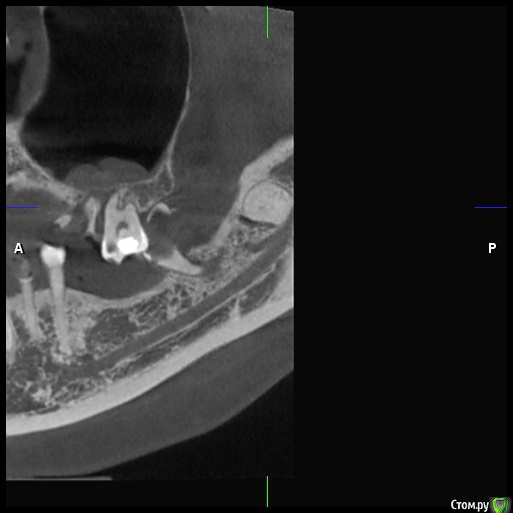

DenisV Опубликовано 18 декабря, 2019 Поделиться Опубликовано 18 декабря, 2019 Уважаемые коллеги, реферативный пациент, после химиотерапии окончил прохождение 2 месяца назад, хочет санировать полость рта (онколог разрешил), обнаружили образование на КТ в ретромолярной области слева. Какое Ваше мнение ? Направить к онкологу? Ссылка на комментарий

Lodkin666 Опубликовано 19 декабря, 2019 Поделиться Опубликовано 19 декабря, 2019 Мне кажется это похоже на сверхкомплектный зуб. Ссылка на комментарий

DenisV Опубликовано 19 декабря, 2019 Автор Поделиться Опубликовано 19 декабря, 2019 Мне кажется это похоже на сверхкомплектный зуб.неоднородной плотности, напрятали это зуб Ссылка на комментарий

Jurai Опубликовано 22 декабря, 2019 Поделиться Опубликовано 22 декабря, 2019 кажется, что зачаток сверхкомплектного или одонтома. Узнайте у пациента нет ли у него снимков прошлых лет - сравнить со свежим. Ссылка на комментарий

Irouil Опубликовано 22 декабря, 2019 Поделиться Опубликовано 22 декабря, 2019 Согласен, похоже на одонтому, чёткая капсула, плотность дентина 2 Ссылка на комментарий